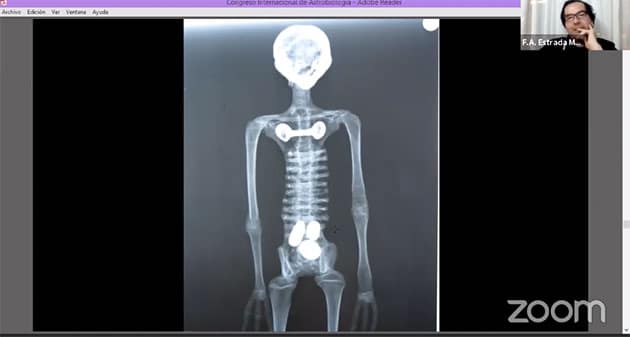

Anhand der Röntgenaufnahme (Abb. 36) ist zu erkennen, dass dieses Wesen überhaupt keine Halswirbel oder sonstige Halsknochen besitzt. Zugleich gibt es aber auch keine Anzeichen für eine diesen Hals und damit den Kopf stützende Muskulatur. Eine weitere anatomische Katastrophe ist der Einbau der Oberschenkel, die wie Arme platziert wurden. Zudem verfügt das Wesen über keine wirklichen Gelenke. Mit Ausnahme des Schädels stammen auch hier alle Knochen von Menschen – in diesem Fall von noch nicht ausgewachsenen Menschen, da sich an den Knochen Wachstumslinien erkennen lassen. Anhand dieser Merkmale schließen die Wissenschaftler, dass der Mensch, dessen Knochen hier verwendet/missbraucht wurden, Ernährungsprobleme hatte.

Albertos Schädel (Abb. 37 l. weiß) ist ähnlich gearbeitet, wie die vorigen Schädel der anderen kleinen Mumien (Abb. 37. r. blau), besteht selbst aber fast ausschließlich aus einem sogenannten Gehirnschädel (Neurokranium), der das Gehirn umschließt. Es finden sich keine weiteren Schädelteile. Die Röntgenaufnahmen (37) zeigt das anschaulich. Erneut vermuten die UNICA-Wissenschaftler, dass die weiße pudrige Farbe auf den Mumien oberflächlich offenkundige Fehler verdecken sollte.

Auch die Machart von Albertos dreifingrigen Händen (Abb. 38), entspricht der voriger Proben (Abb. 29, 30).